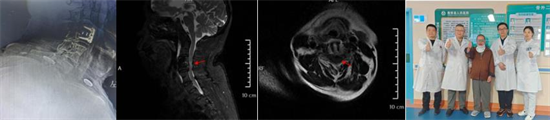

術(shù)后復(fù)查顯示內(nèi)固定位置良好、椎管減壓充分,患者自覺癥狀明顯緩解

為確保手術(shù)成功,骨科二區(qū)專家團隊與湘雅三醫(yī)院苗驚雷教授緊密協(xié)作,在麻醉科和手術(shù)室的配合下,成功為患者實施頸前路椎間盤切除術(shù)+椎管擴大減壓術(shù)+植骨融合內(nèi)固定術(shù),患者術(shù)后即感四肢肌力明顯改善,目前恢復(fù)良好,已順利出院。